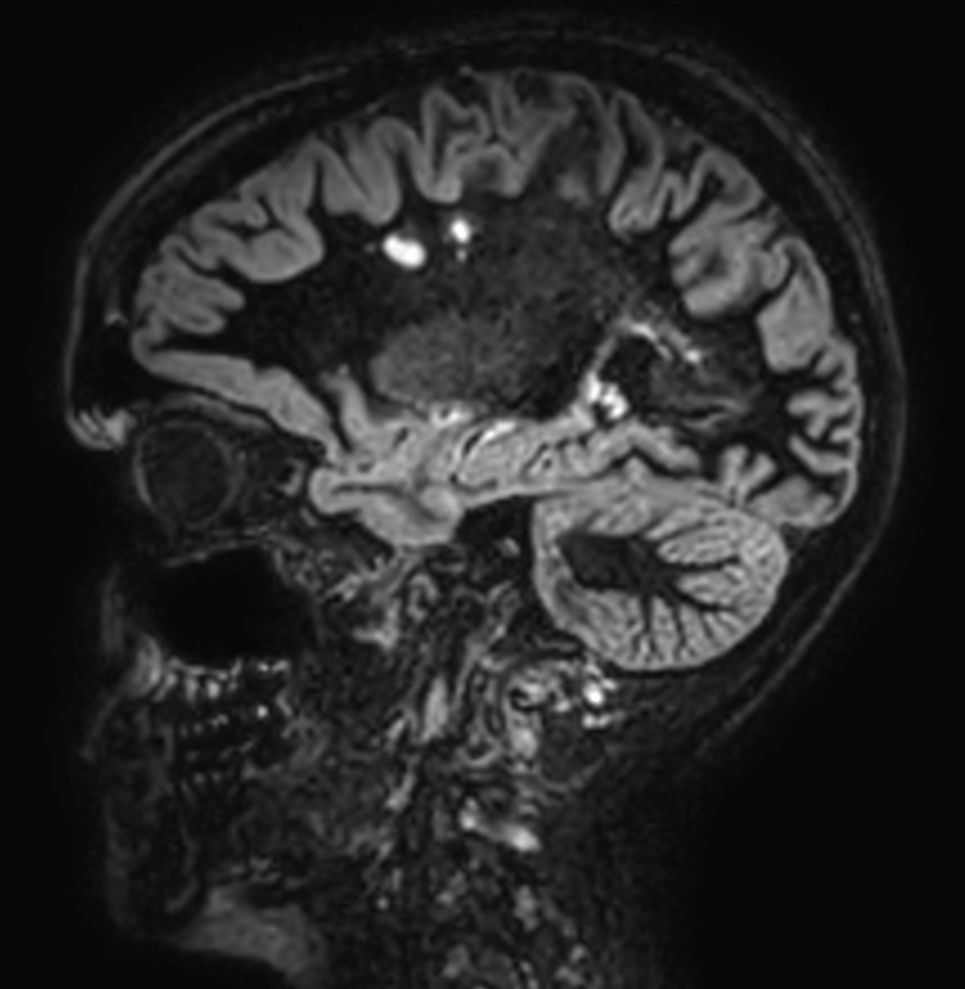

SWI sequence has a high sensitivity to enhance contrast for deoxygenated (venous) blood or calcium deposits. This may help, when used in combination with other clinical information, in the diagnosis of various neurological pathologies. 3D imaging lets you acquire high resolution data in multiple directions in one scan. Isotropic voxel size enables reformats in any plane without loss of resolution. FLAIR* requires offline post processing combining the contrast of 3D FLAIR and 3D SWI EPI into a single image. This enables the visualization of Central Vein Sign, mapping subcortical veins onto 3D FLAIR contrast images.